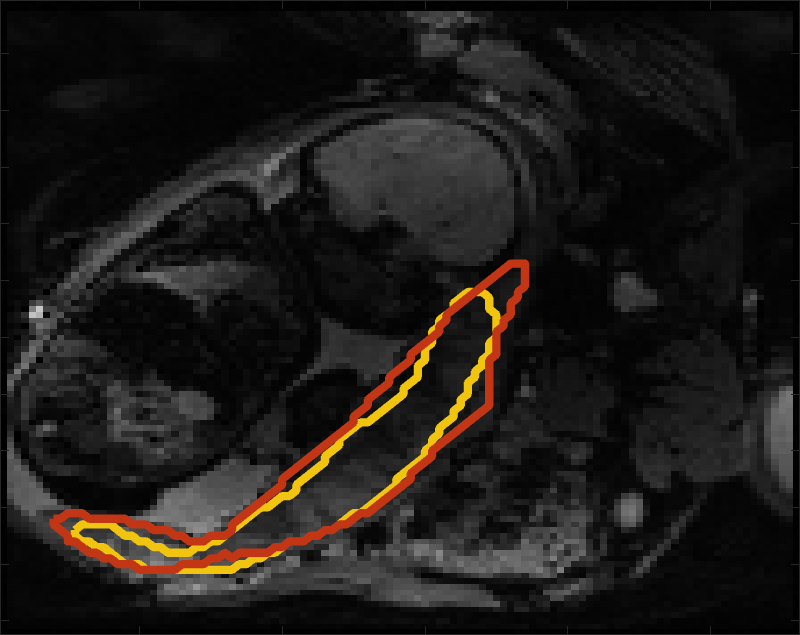

Fig 3 compares the predicted label maps with ground truth on subjects with increasing Dice scores using the BW-CE model. The model accurately identifies the location of the placenta, but in the worst cases misses boundary details.